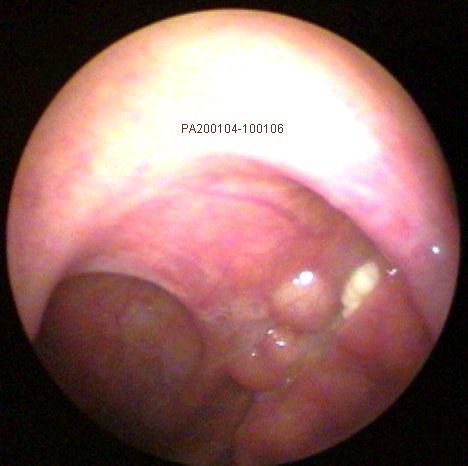

JFC Otitis media serosa de origen disbárico.

JFC Otitis media serosa izquierda.